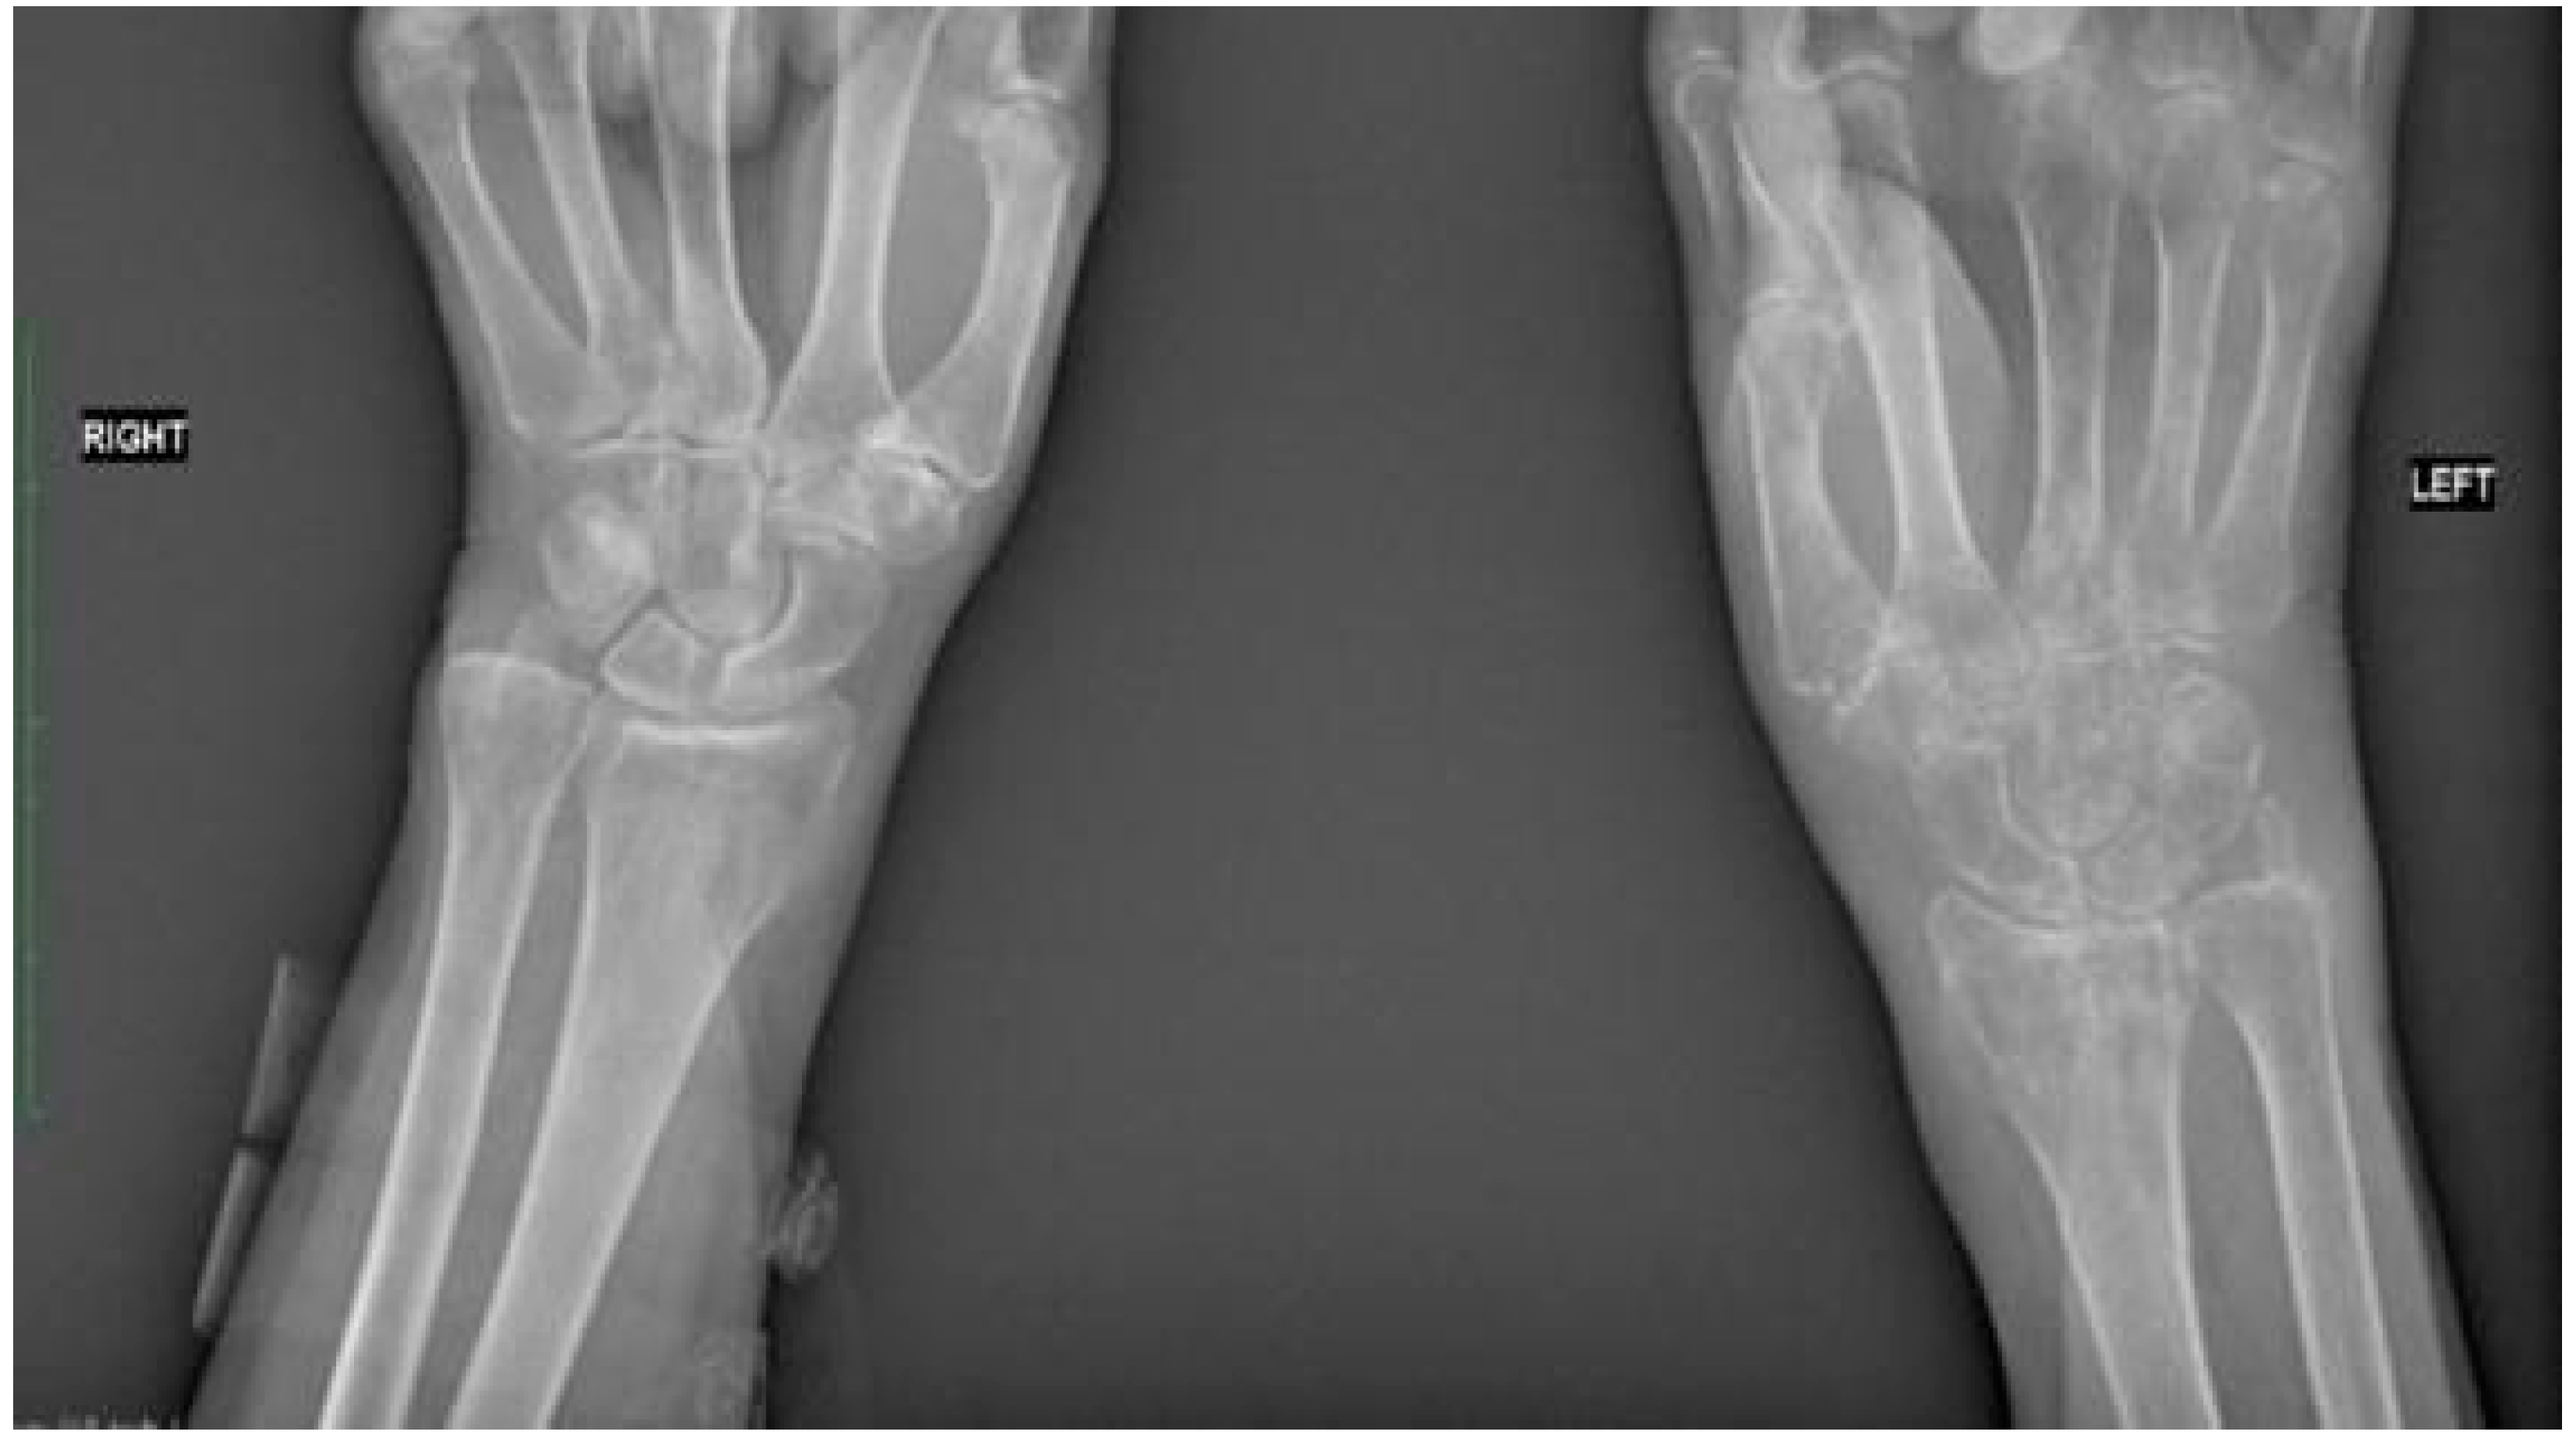

2.2. Fracture and Initial Treatment